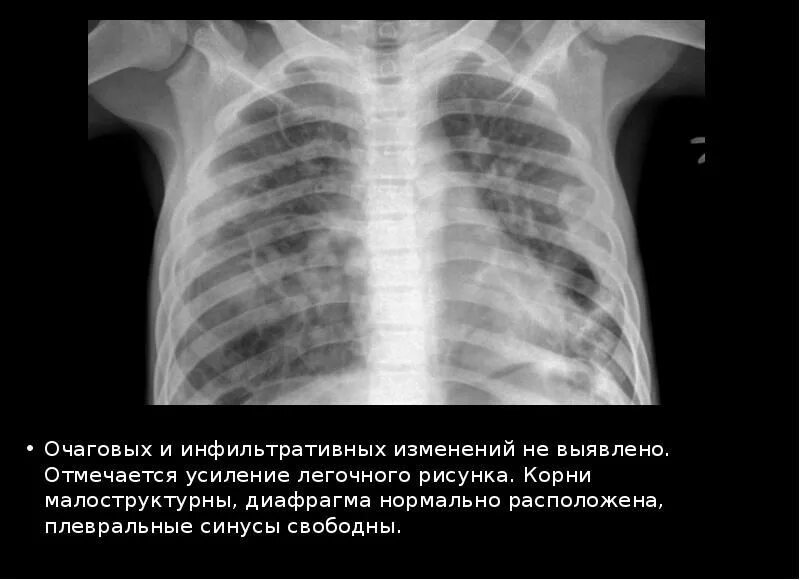

Очаговых и инфильтративных изменений не выявлено